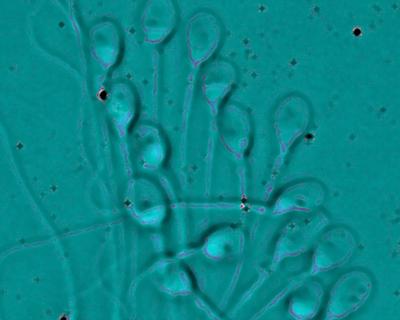

Il metodo di selezione dello sperma include l’esame morfologico degli spermatozoi ad alta risoluzione con microscopio ad immagine ingrandita di circa 5 volte in più rispetto a quello utilizzato fino ad ora.

In questo modo, si selezionano gli spermatozoi con morfologia e dimensioni di buona qualità genetica. Ecco perché gli embriologi che si occupano di quest’esame devono essere dotati di formazione specializzata. Successivamente, gli spermatozoi selezionati sono introdotti negli ovuli con il metodo ICSI.